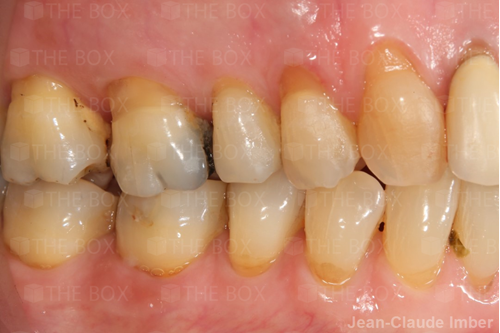

A new case was made public by Jean-Claude Imber check it out here.